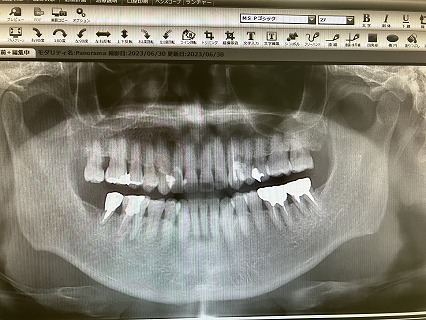

2023.06.30より 圭介歯科 0968-62-1822

2024年7月5日(金) 右上奥歯の虫歯が痛んだ

23.7.21 検査 PDF   23.10.27 検査 PDF